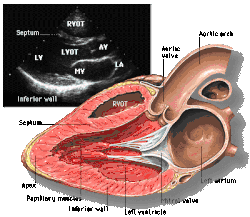

![]() Subcostal four chamber | ![]() Apical four chamber | ![]() Parasternal long axis | ![]() Parasternal short axis | ||||||||

| Each figure contains a TTE with a black background, and a corresponding colored illustration. | Patrick J. Lynch and C. Carl Jaffe, Yale University, 2006. | ||||||||||

| Click on a figure to enlarge it and see some parts of the heart identified. RV, right ventricle; LV, left ventricle; RA, right atrium; LA, left atrium; TV, tricuspid valve; MV, mitral valve; AV, aortic valve; RVOT, right ventricular outflow tract; LVOT, left ventricular outflow tract | |||||||||||